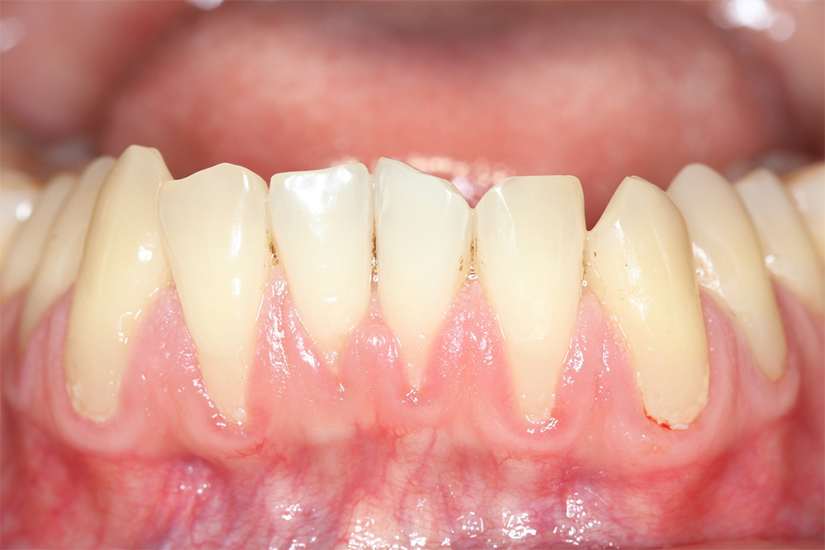

În cazul unei retracții gingivale, poți observa cu ochiul liber că un dinte pare mai lung, fie din cauza gingiei căzute, fie pentru că nivelul gingiei s-a ridicat, dezvelind din rădăcina dintelui. La atingere, vei simți o adâncitură mică între gingie și dinte.

Pe lângă aspectele ce țin de estetica zâmbetului, te mai poți confrunta cu sensibilitate dentară la consumul de alimente sau băuturi reci, calde ori dulci și durere. Dacă ai oricare dintre aceste simptome, este extrem de important să mergi cât mai repede la medicul stomatolog.